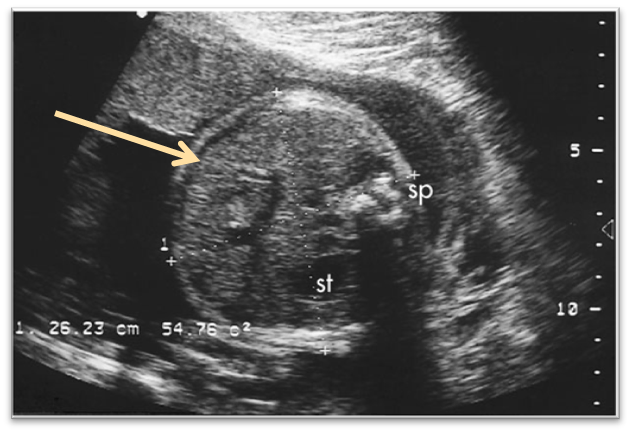

What view is this?

outflow tract